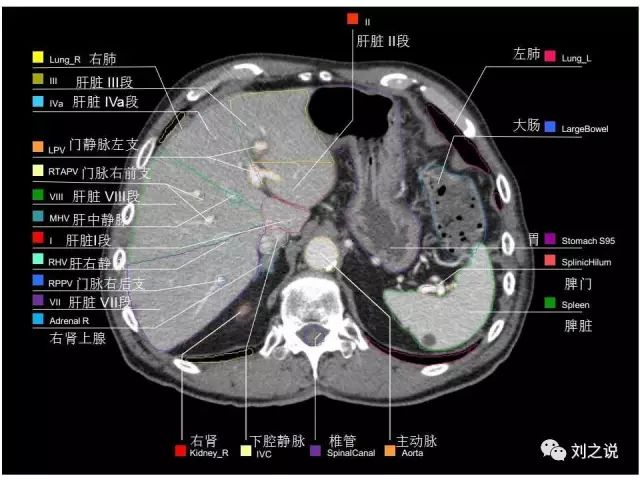

参考RTOG共识和3D-body解剖。

来源:刘之说